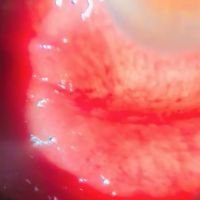

- Florencia Miranda